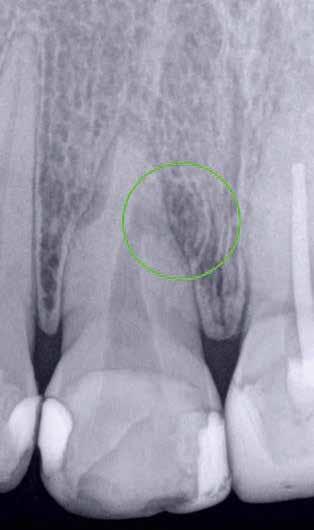

ai felvételek segítségével viszonylag jól el lehet különíteni a külső rezopció okozta ártalmaktól. A belső rezorpciótól szenvedő fogak esetében a radiológiai felvételek excentrikus irányból történő elkészítése során a rezorptív lézió a fog gyökércsatornájával egy irányba mozdul el a felvételen, míg külső rezorpció esetében le fog vetülni a gyökércsatornáról. 1999 márciusában egy 47 éves hölgy páciens arcduzzanattal kereste fel a rendelőnket. Klinikai vizsgálat során a jobb felső nagymetszőfog (11) kopogtatásra való érzékenységét tapasztaltuk. A felső front régióról készült periapikális felvételeken a frontfogakban lévő nagy kiterjedésű III. és IV. osztályú restaurátumokat észleltünk. Az 11-es fog gyökércsúcsa körül periapikális felritkulás volt látható. A 21-es fognál a gyökér középső harmadában belső rezorpciót észleltünk (13. ábra). A páciens kérdésünkre elmondta, hogy a bal felső nagymetszője közel 35 évvel ezelőtt traumás sérülést szenvedett. Mivel abban az időben CBCT-felvételek készítése nem volt számunkra elérhető, így a klinikai adatok alapján azt feltételeztük, hogy a rezorptív lézió bukkális irányba perforálta a gyökércsatorna falát, majd ezt követően az ezt a területet fedő bukkális csontállományt is destruálta.

A frontrégióban végzett szenzibilitás vizsgálat is megerősítette a 11 fogban a fogbélelhalás diagnózisát. Az 11-es fog endodonciai kezelése során a gyökércsatorna biokemo-mechanikai megmunkálását követően a gyökércsatornát meleg vertikális kondenzációs technikával zártuk. A bal felső nagymetsző esetében a gyökércsatorna megmunkálását a rezorpciós üreg koronális határáig végeztük, majd a megmunkált csatornaszakaszt fehér MTA-val töltöttük fel (14. ábra). Amennyiben ennek a fognak a kezelését ma kellene elvégezni, akkor az EndoSequence BC puttyt (Brasseler) használnánk a gyökértömés elkészítésére. Ezenkívül azt is megemlítenénk, hogy manapság egyre gyakrabban próbál-

13. ábra: A periapikális felvételen jól lekövethető a 11-es fog gyökércsúcsa körül látható radiolucens terület körvonala. A 21-es fog gyökerének középső harmadában pedig belső rezorpció jelenlétére utaló jelek észlelhetőek. A rezorptív lézió frontális és laterális irányban is áttörte a csontos falakat, amely következtében a gyökeret körülvevő csontállomány is károsodott. – 14. ábra: A posztoperatív felvételen jól megfigyelhető a 11-es fogba helyezett gyökértömés. A 21-es fog ellátása során a gyökércsatorna megmunkálását csak a rezorptív defektus koronális határáig végeztük. A gyökércsatorna zárására fehér MTA-t alkalmaztunk. – 15. ábra: A 11-es fog gyökércsúcsa körül látható felritkulás teljesen eltűnt. A rezorptív defektus mérete csökkent, valamint a rezorpciós üreg csontosodására utaló jelek is megfigyelhetőek. – 16. ábra: A saggitalis irányú CBCT-metszeten jól látható, hogy a 21-es fogat ép és jól megtartott bukkális kortikális csont fedi. A rezorpciós üreg mérete jelentősen csökkent, valamint az üreg kalcifikálódott anyaggal való telődése is megfigyelhető volt.